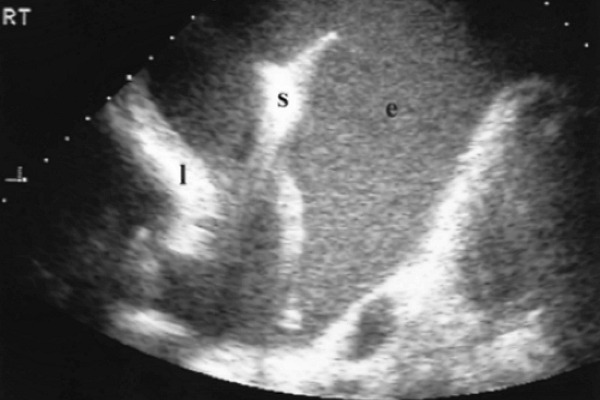

Поверхность легкого лоцируется как широкая, хорошо выраженная гиперэхогенная линия, расположенная несколько глубже париетальной плевры. Во время сканирования видимый контур воздушного легкого смещается в соответствии с дыхательными движениями пациента. Плевральный синус (просвет между листами плевры) с небольшим количеством жидкости, на эхограмме выглядит как тонкая анэхогенная щель, в которой определяется подвижная часть легкого.

Сканирование из субкостального доступа, позволяет увидеть печень, диафрагму и селезенку. При вдохе линия диафрагмы, имеющая толщину около 0,5 см, смещается вниз, при выдохе возвращается в прежнее положение. Супрастернальный доступ, позволяет оценить состояние органов средостения. При этом крупные сосуды и лимфатические узлы определяются как эхонегативные структуры, четко выступающие на фоне эхопозитивной жировой клетчатки.